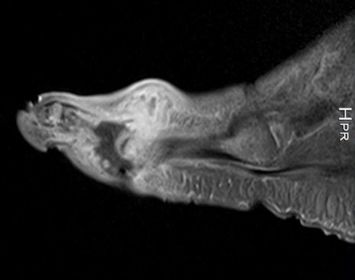

What does this indicate? | Increased signal and enhancement of the soft tissue plantar to the proximal phalanx suggestive of subcutaneous infection without abscess |

What does this indicate? | Increased signal and soft tissue distension dorsally representing subcutaneous abscess communicating with associated with plantar ulcerative defect. |